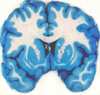

What type of posturing is this person displaying? [1]

Which arteries do the arrows point to? [1]

Lenticulostiate arteries